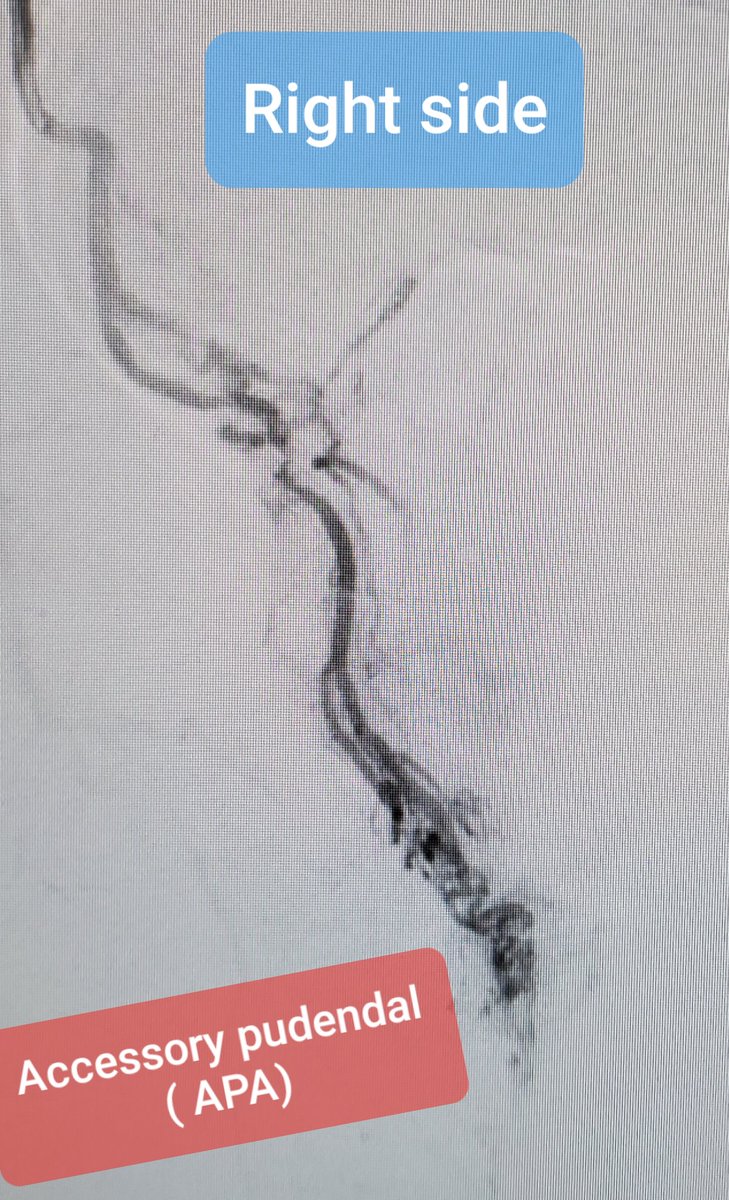

#PAE during a#RadialFirst course is humbling! One

patient with SEVERAL #PAE vascular#signatures.... Coil embo, upsize, Superselective embo and done! pic.twitter.com/l1KMRnkACu